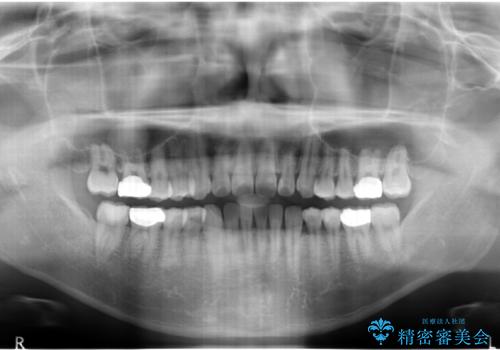

前歯のねじれ 上だけ部分矯正でコストダウン

- 前歯のねじれを部分矯正で治療しました。

奥歯のかみ合わせを変えずに、費用を抑えて短期間に治療したい方におすすめです。

矯正前に、後戻り防止のため上唇小帯の処置を行っています。

奥歯のかみあわせも問題なく、また、下の前歯のがたつきが元からない場合は上の部分矯正が十分可能です。

上下親知らずの抜歯や虫歯処置も矯正前後で行っています。